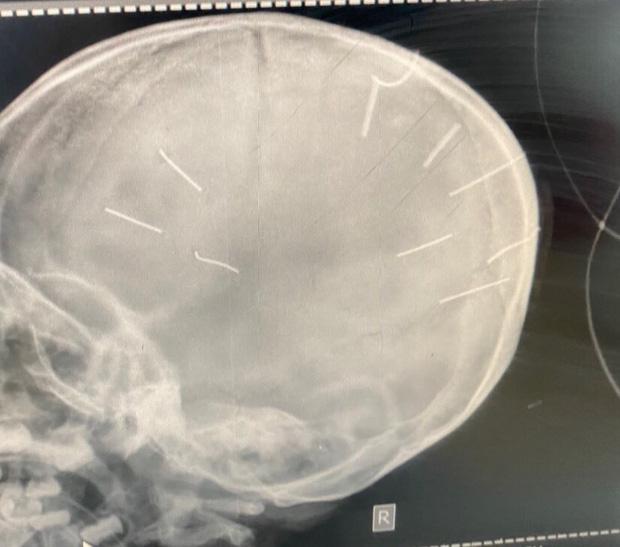

Hình ảnh chụp chiếu hộp sọ bé gái với 9 hình thể nghi là đinh (Ảnh: Bệnh viện Đa khoa huyện Thạch Thất cung cấp).

Theo ông Kiên, Bệnh viện Đa khoa Xanh Pôn đã tiến hành chụp chiếu, nhận thấy có những hình ảnh giống như đinh gỗ ở sọ và tổ chức não, tổng cộng 9 cái.